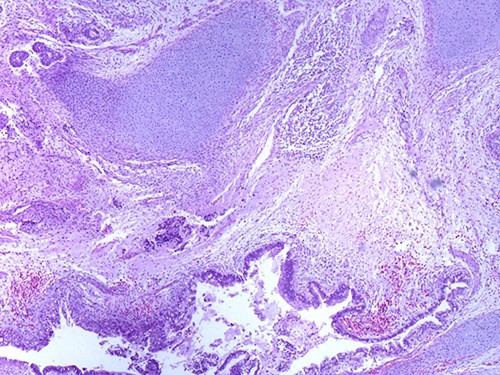

A 46-year-old woman, without clinical antecedent, presented with a tumor in the inner side of the left cheek which had rapidly grown for 3 weeks. Physical examination revealed an ulcerating mass measuring 4 × 3.5 cm, well-circumscribed, fleshly, with a white surface. There was submandibular lymphadenopathy, ranging in dimension from 1 to 1.5 cm in diameter. Magnetic resonance imaging (MRI) scan revealed the tumor of the cheek without mandibular bone infiltration or sinonasal involvement (Fig. 1). Chest computed tomography and abdominal ultrasound scan were unremarkable. An excisional biopsy was performed. Pathological examination showed a neoplastic proliferation composed of mixture of mature benign epithelial components, such as intestinal type, respiratory and squamous epithelia, and mature mesenchymal components, such as muscular tissue and cartilage (Fig. 2) and neuroglial tissue. In addition, immature and malignant tumor components were found such as small blue tumor cells resembling primitive neuroectodermal tumor (Fig. 3), adenocarcinoma and sarcoma with muscular and cartilaginous differentiation (Fig. 4). This tumor infiltrates the skeletal muscle with free margins. Immunohistochemically, epithelial components were positive for pankeratin; mesenchymal components showed desmin, myogenin and S-100 positivity and the primitive neuroectodermal tumor component was positive for NSE, CD99, GFAP, synaptophysin and focally for chromogranin. SALL4 was negative. The resected submandibular lymph nodes were devoid of malignant infiltrate. The diagnosis of TCS was established and the patient was treated by combined chemotherapy (cisplatine +5 fluorouracil) and radiation therapy. No recurrence was noted 6 months after treatment.

Photomicrograph of primitive neuroectodermal component with neural rosettes (magnification at ×400).